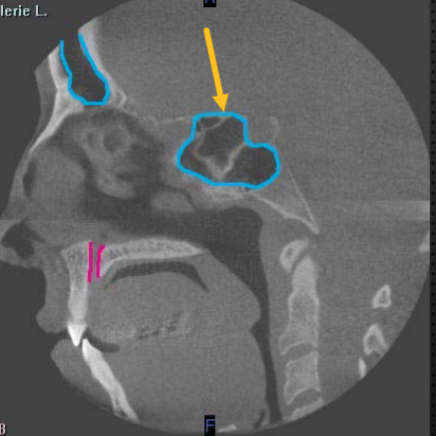

zygomatic arch

what is indicated by the YELLOW

middle turbinates/concha

identify the structure